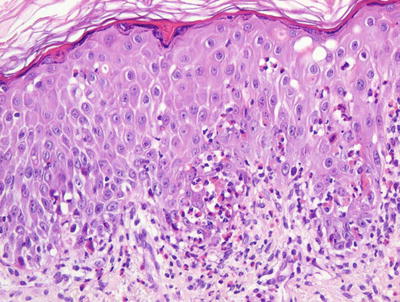

Histologic features in Bloom syndrome resemble those seen in lupus erythematosus. There is interface dermatitis, and the epidermis demonstrates extensive basal vacuolization with exocytosis of lymphocytes (Figs. 17.15 and 17.16). Melanophages are present in the dermis with a moderately intense superficial perivascular lymphocytic infiltrate. Dilated capillaries are present, resulting in clinically apparent telangiectasias [105].

Fig. 17.15

Bloom syndrome is characterized by an interface dermatitis with abundant dying keratinocytes within the basal layer of the epidermis

Fig. 17.16

A lymphocytic infiltrate is present in the papillary dermis and extends into the epidermis with dead keratinocytes in Bloom syndrome

The histologic differential diagnosis includes lupus erythematosus and other interface processes. Unlike lupus erythematosus, basement membrane thickening and mucin deposition are not seen in Bloom syndrome skin biopsies. Direct immunofluorescence stains do not reveal immunoglobulin deposits at the dermal-epidermal junction [105]. A phototoxic drug eruption could also be considered. Clinical correlation is the best way to make this distinction because the histologic findings in these entities are identical .